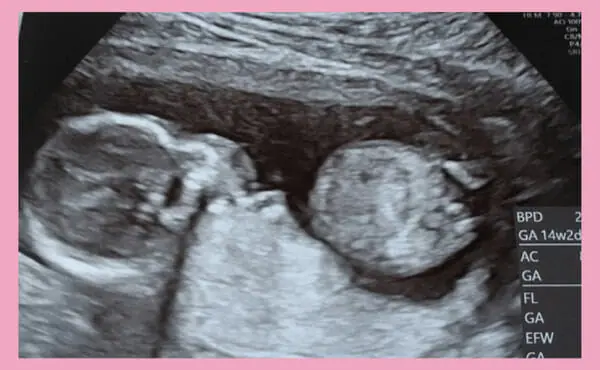

妊娠14周时,胎儿的CRL(头长)约90mm、体重估计为20〜25g左右。腹部超声检查可能显示出胎儿的胃泡,膀胱里存有尿液。妊娠14周时,胎儿在羊水中转来转去,开始主动活动四肢和运动。但是要感觉到胎动,还要等到妊娠18周以后。

妊娠14周时的超声照片。